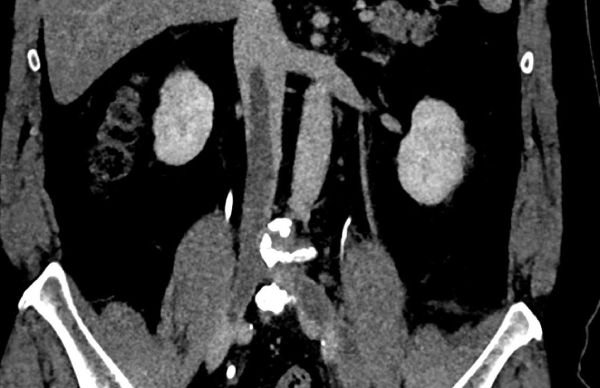

Назначаются общие лабораторные исследования, выявляющие признаки воспаления, других нарушений. Может проводиться обзорное УЗИ, КТ или МРТ брюшной полости, малого таза, грудной клетки.